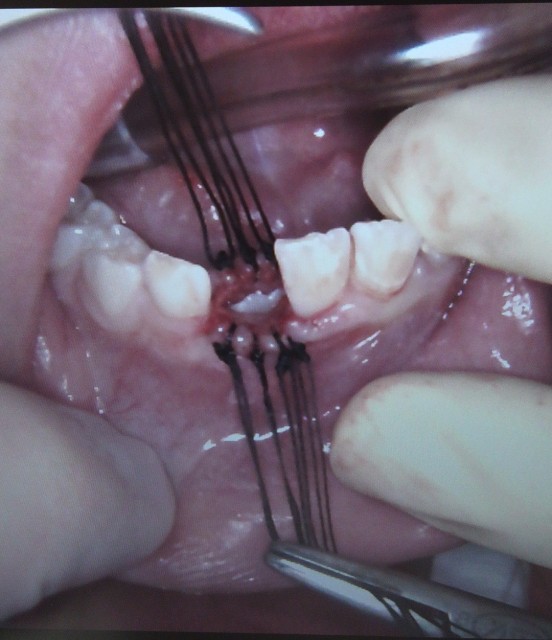

肥満手術について - 広島赤十字・原爆病院公式サイト。

好きです: 95